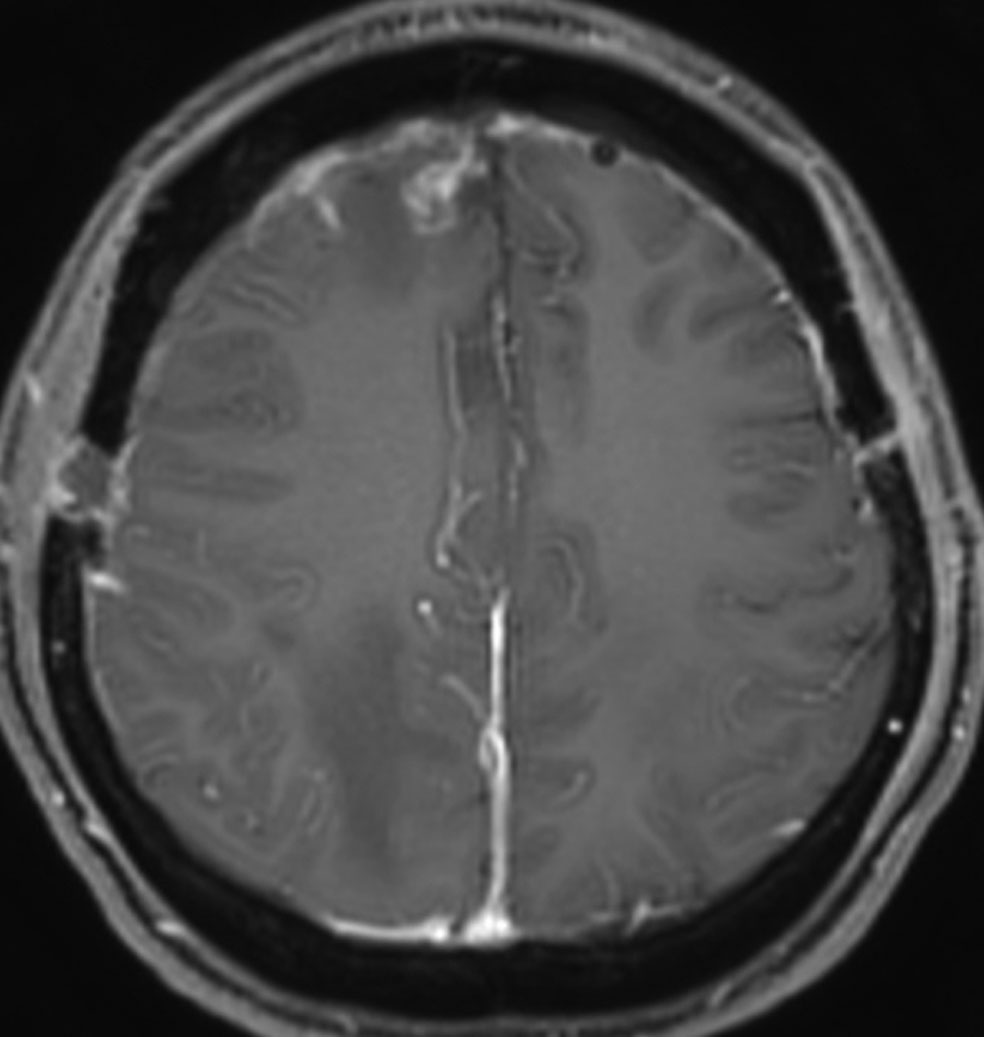

多発例,NF-2ではないもの

30代で下肢の局所てんかん発作で発見されました。テント上硬膜の腫瘍化です。数えれば総数で30個以上はあったでしょう。このタイプは手術で硬膜を広範囲切除(ほとんど全頭蓋冠)することで治すことができます。

H字状皮膚切開で広範囲両側前頭登頂開頭をして,穹窿部と傍矢状洞部髄膜腫をほとんど摘出してしまいました。上矢状洞は開存していたので残してあります。